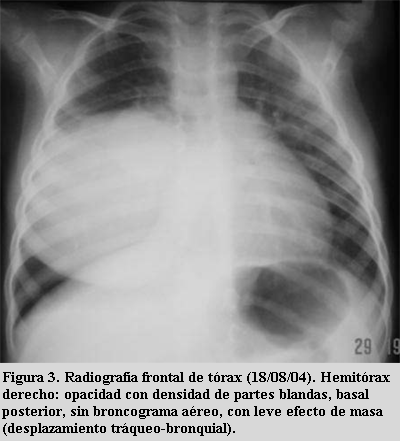

Blastoma pleuropulmonar en un preescolar: Una causa poco ... .